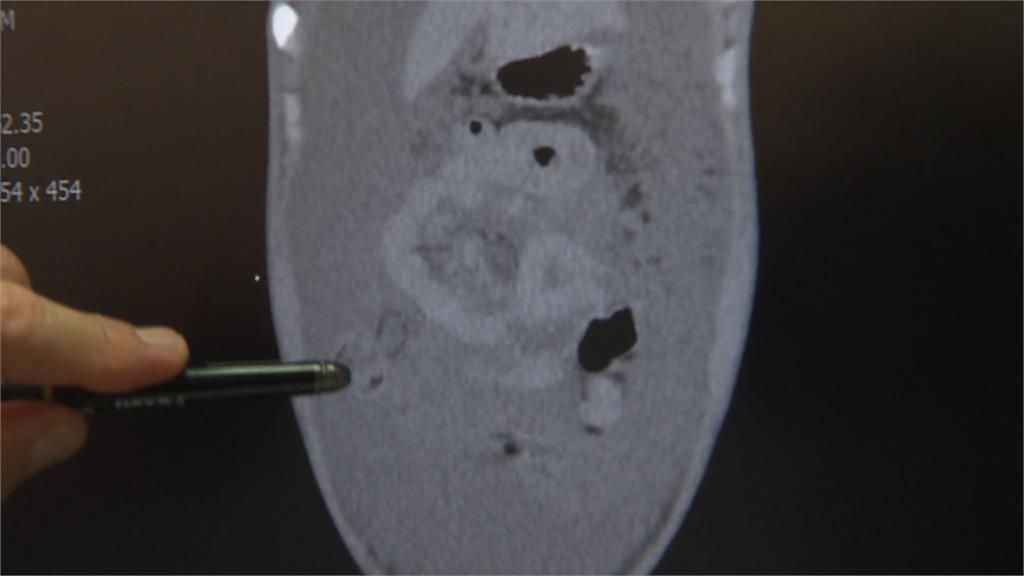

15歲的少年因為不明腹痛到院急診,檢查後發現少年腹水散佈在肚子裡,而且還有一顆約8公分的腫瘤,罹患大腸癌,已經第四期。